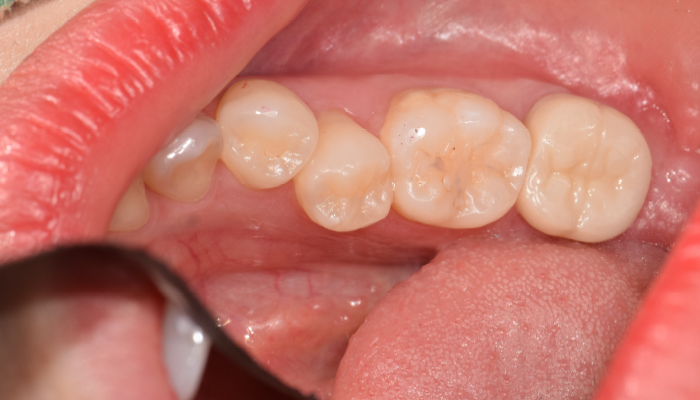

충치치료 전후 사례

• 치료 전

치료 후